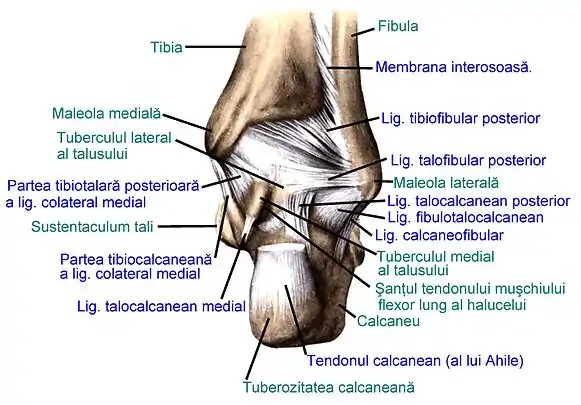

Articulațiile talusului și inserțiile ligamentare

Talusul este legat de oasele vecine prin 3 articulații: articulația talocrurală, articulația subtalară și articulația talocalcaneonaviculară. Articulația talocrurală leagă oasele gambei (tibia și fibula), prin intermediul talusului, de scheletul piciorului. Articulația subtalară unește fața inferioară a talusului și fața superioară a calcaneului prin intermediul fețișoarelor lor articulare posterioare. Articulația talocalcaneonaviculară unește talusul de calcaneu și navicular.[1][2][3]

Pe talus nu se inseră nici un mușchi, ci numai 11 ligamente sau fascicule ligamentare ale articulațiilor talocrurală, subtalară și talocalcaneonaviculară; tendoanele mușchilor trec pe lângă el, spre a se insera pe diferitele oase ale piciorului. Ligamentul calcaneonavicular plantar nu se inseră pe talus, însă are pe fața lui superioară (dorsală) un fibrocartilaj triunghiular denumit navicular (sau fața articulară superioară a ligamentului calcaneonavicular plantar), pe care se sprijină capul talusului.[1][2][3][4][5][9]

Ligamentele articulațiilor piciorului drept, văzute lateral (după Sobotta's Atlas and Text-book of Human Anatomy 1909)

Ligamentele articulațiilor piciorului drept, văzute medial (după Sobotta's Atlas and Text-book of Human Anatomy 1909)

Ligamentele articulațiilor piciorului drept, văzute posterior (după Sobotta's Atlas and Text-book of Human Anatomy 1909)

Articulația talocrurală și articulația subtalară; secțiune frontală (după Sobotta's Atlas and Text-book of Human Anatomy 1909)